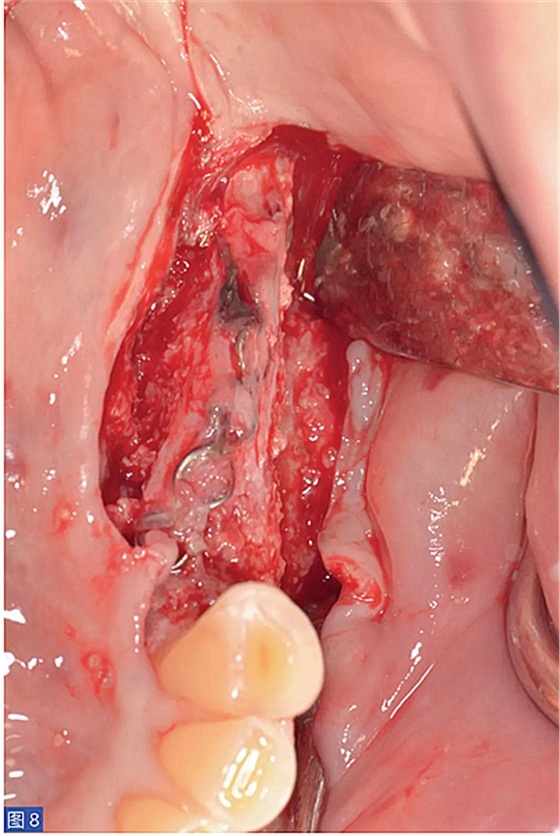

圖8:病例1. 術(shù)后6 個(gè)月的再生組織。咬合面觀。